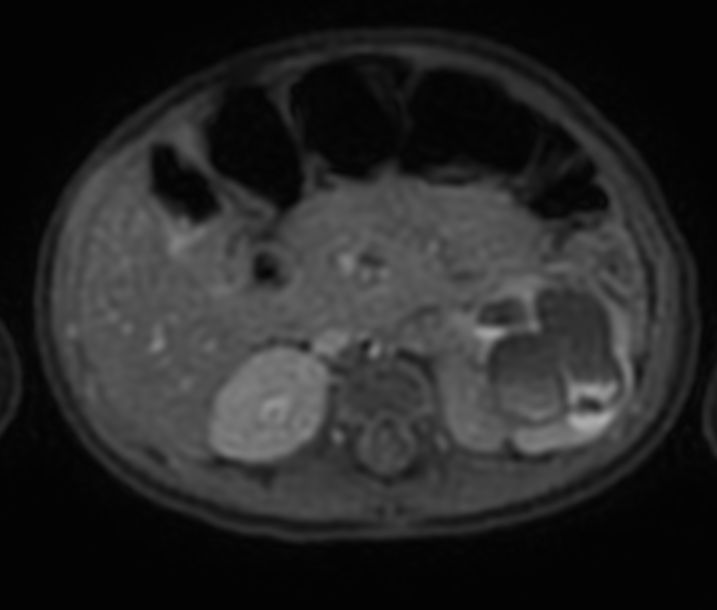

Axial T2w MultiVane XD SPAIR